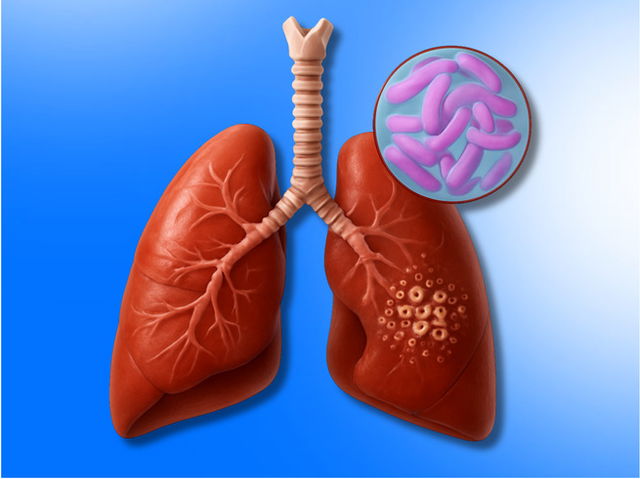

La Tuberculosis es una enfermedad infecciosa causada por una bacteria que afecta principalmente a los pulmones, aunque también puede afectar a otras partes del cuerpo. Se transmite a través del aire cuando una persona infectada tose, estornuda o habla.

A pesar de que se puede prevenir y tratar, sigue siendo una de las enfermedades infecciosas más extendidas en el mundo.